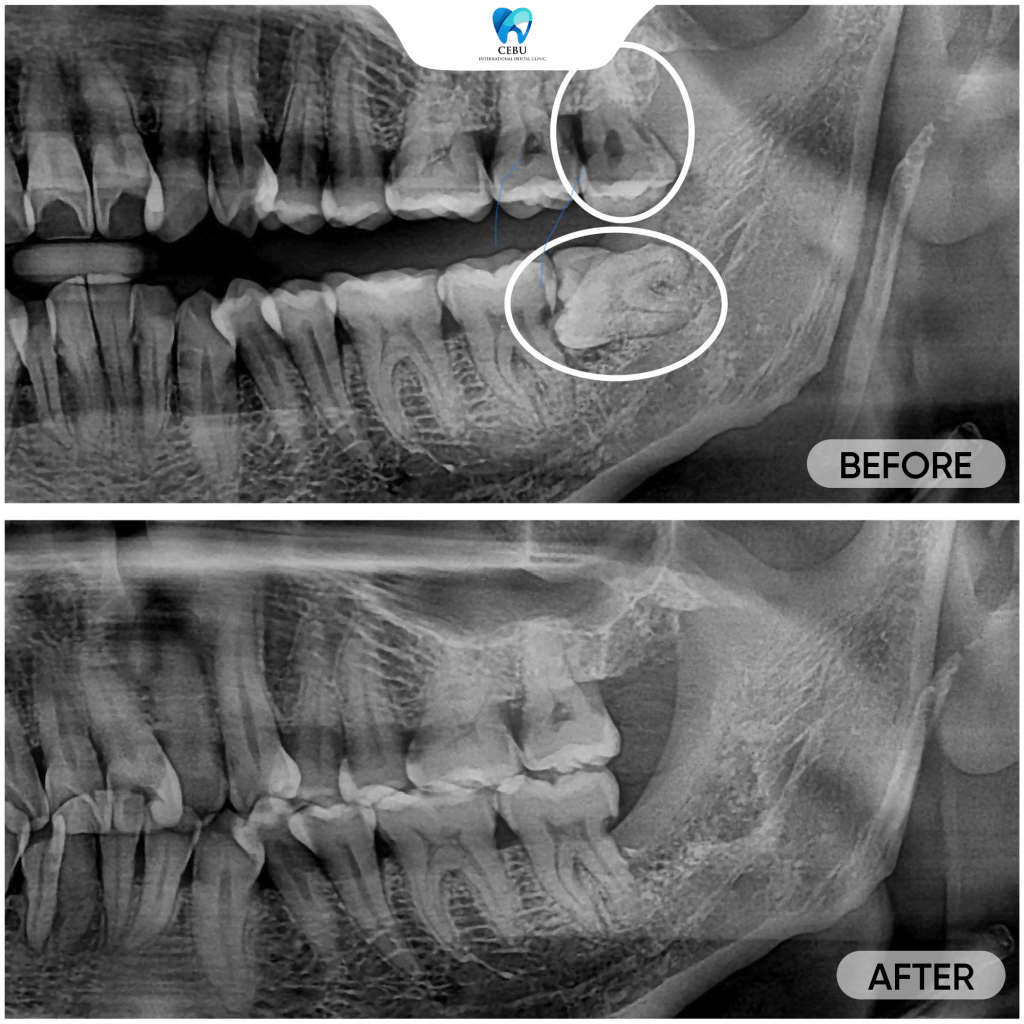

Serious dental risks you face when leaving wisdom teeth untreated today A Wisdom Tooth may seem harmless at first, but improperly erupted wisdom teeth can ...

Serious dental risks you face when leaving wisdom teeth untreated today A Wisdom Tooth may seem harmless at first, but improperly erupted wisdom teeth can lead ...